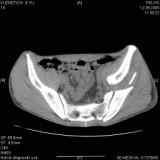

Уважаемые коллеги! Хотелось бы услышать совет по тактике лечения представлленого больного.Поступил после лечения в одном изотделений области. Травма 2,5 месяца назад. После выведенияиз шока был произведен остеосинтез перелома бедра, предплечья, до перевода к нам проводилосьвытяжение по оси шейки бедра за стержень, введенный в большой вертел. На сегодня деформацияригидна, клинически мобильности не определяется. Заранее признателен. P.S. Данный вид травм не включен в перечень "высокотехнологичных операций", направить длялечения по квотам Минздрава очень сложно.

Это обзорные и косые снимки

С уважением,

Leonid